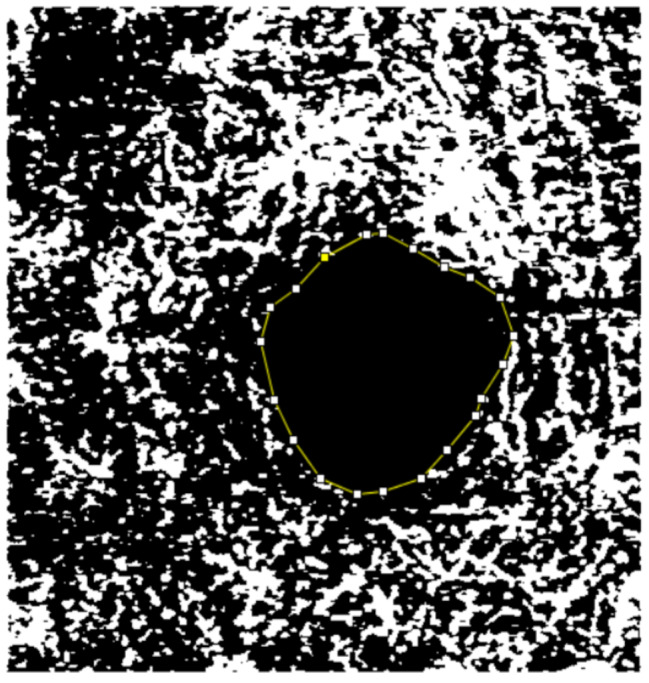

Methods: A cross-sectional comparative case-control study (unpaired) was carried out at two tertiary hospitals. All subjects underwent optical coherence tomography angiography (OCTA) examination (DRI OCT Triton Swept Source, Topcon, Japan). The average VD in the superficial capillary plexus (SCP) and the deep capillary plexus (DCP), the FAZ area (mm2) in SCP, and DCP were taken into analysis. The time since the diagnosis of T2DM was used to stratify patients with diabetes between 5 and 10 years and those with a diagnosis of more than 10 years.

Results: Compared to non-diabetic controls, the parafoveal VD in both SCP and DCP was significantly reduced in the eyes of T2DM patients without clinical DR (p < 0.001). Additionally, the VD was also statistically reduced in T2DM diagnosed more than 10 years ago compared to T2DM cases diagnosed between 5 and 10 years ago (p < 0.001). The FAZ area in both plexuses was larger in T2DM eyes compared to controls (p < 0.001). The FAZ area was enlarged in DCP (p = 0.04), but there was no significance of FAZ area in SCP when comparing patients with T2DM diagnosed between 5 and 10 years ago to those diagnosed more than 10 years ago (p = 0.06).

Conclusion: In diabetic patients with long-term diagnosed disease, OCTA was shown to be capable of detecting preclinical microvascular foveal abnormalities prior to the development of clinically apparent retinopathy. According to our findings, OCTA has the potential to be a promising instrument for the early detection of vascular micro-abnormalities and the routine screening of diabetic eyes.